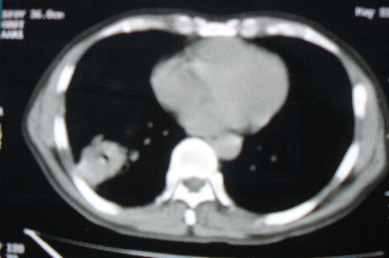

ct10716,男,59岁。发热咳嗽一天,咯血一次入院。

病灶中心有低密度,气体,病灶周围炎性浸润可能为肺脓肿,量体温、查个痰就是了,但肺脓肿一般都多少会有点兄水的。左肺下局部密度减低,小叶中心肺气肿。

病灶边缘较模糊,中心见低密度影及少量气影,宽基与胸膜相连,周围见炎性浸润,考虑右下肺脓肿。

病灶边缘较模糊,中心见低密度影及少量气影,宽基与胸膜相连,周围见炎性浸润,考虑右下肺脓肿。建议治疗后复查。

右下肺病灶,边缘模糊,中心见低密度坏死区及气体影,结合病史较短,以发热为主,考虑右下肺脓肿,建议抗炎治疗后复查。